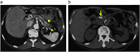

1. 膵管内の結石(膵石)を認めた場合と、膵全体に分布する複数かつびまん性の石灰化を認めた場合は慢性膵炎と診断できる(推奨度1)

1. 加齢現象に伴い膵石が観察される場合がある。

1. 石灰化を伴った膵腫瘍がまれに存在する。